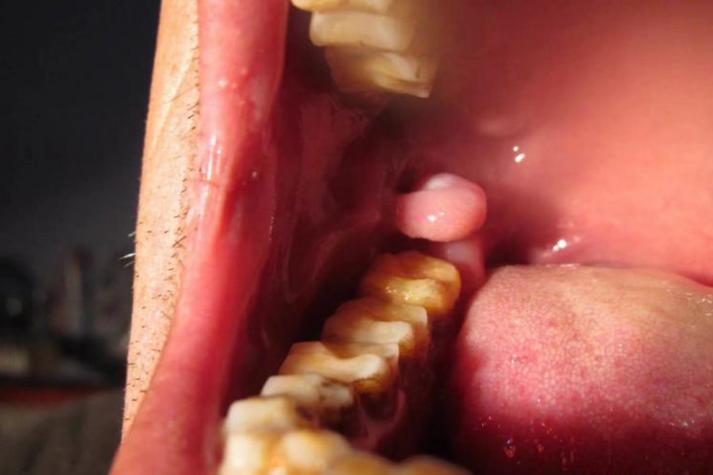

- 外观:生长速度非常快,颜色鲜红或暗红,表面光滑,质地柔软,容易出血。

- 会消失吗?:极有可能自行消退,但风险很高。

- 理论上,如果引起它的急性炎症或刺激源(如咬伤伤口愈合了)被去除,身体自身的免疫系统可能会将其清除,息肉会萎缩消失。

- 现实中:由于其易出血的特性,很容易在刷牙、吃东西时被碰破,导致出血和二次感染,反而会刺激它长得更大,不建议等待它自行消失。